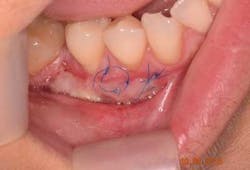

The free gingival graft was secured using 6.0 Prolene sutures in single interrupted fashion (figure 5). The gingival margin of the vestibular mucosa was fixed to the periosteum using the same suture. The donor site was sutured with 4.0 chromic gut resorbable sutures in single interrupted fashion (figure 6).